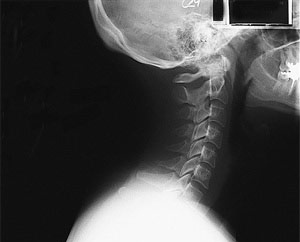

Radiography is the use of x-ray radiation to produce 2-dimensional images of internal body structures to help physicians diagnose and treat various medical conditions.

X-ray imaging is painless and has been in use since 1895. Medical uses of x-ray are many, ranging from imaging the skeletal system of bones, to imaging soft tissues such as lungs with chest x-rays, or intestinal or urinary system structures with contrast materials.

- X-ray assists doctors in the identification and treatment of a broad range of conditions, including fractures, arthritis, joint injuries, etc.